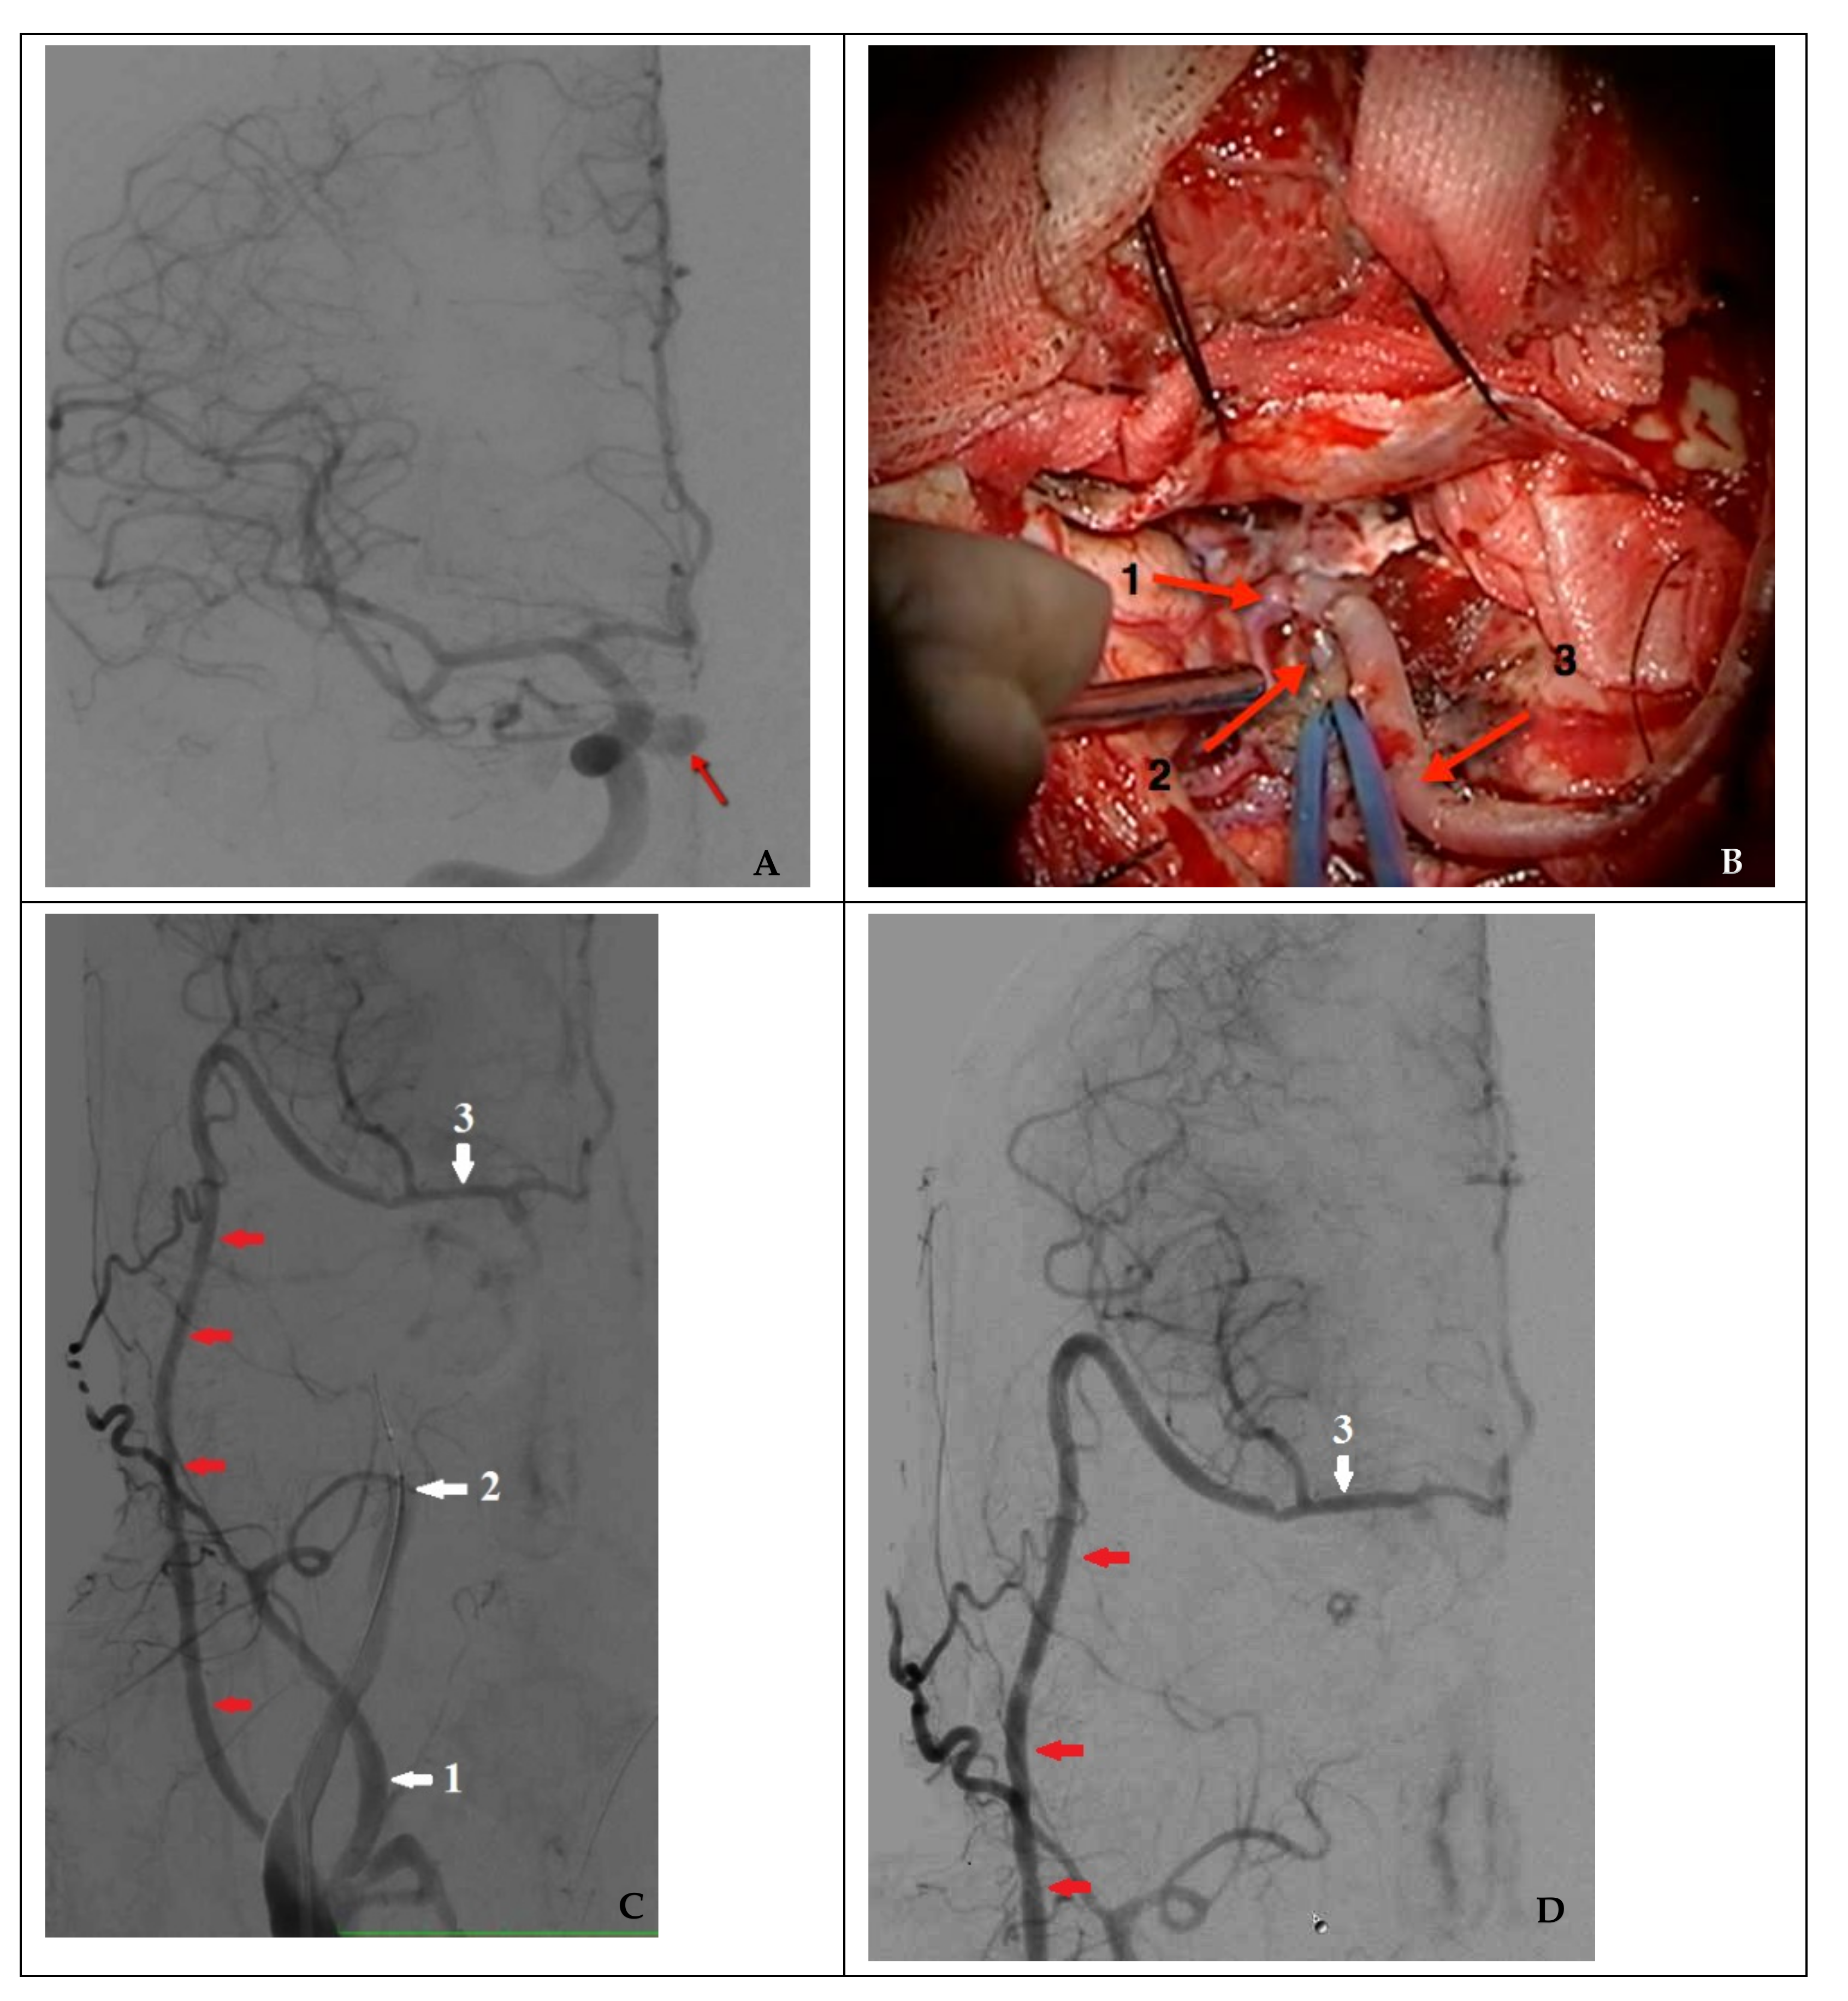

In the case of nonsufficient collateral circulation, the approach to closing the defect required maintaining the blood flow in the basin of the injured artery (reconstructive surgery) or replacing the blood flow (bypass) in the MCA basin on the ipsilateral side: in one case, the patient underwent a stent-graft procedure (Figure 4), and one patient underwent a high-flow bypass followed by ICA occlusion using microcoils (Figure 5).

Figure 5. Combined treatment in a case of nonsufficient circulation (clinical case 8). (A) Angiography of the right ICA (the arrow indicates a false aneurysm), (B) view of a high-flow bypass with right MCA M2 segment bifurcation (1: frontal branch of M2; 2: distal sections of the temporal branch of M2; and 3: radial artery as the graft), (C) functioning high-flow bypass (indicated by red arrows) during a temporary test ICA occlusion, and (D) control angiography after endovascular occlusion of a false aneurysm and the injured right ICA (1: external carotid artery; 2: internal carotid artery occluded by a balloon; and 3: middle cerebral artery).